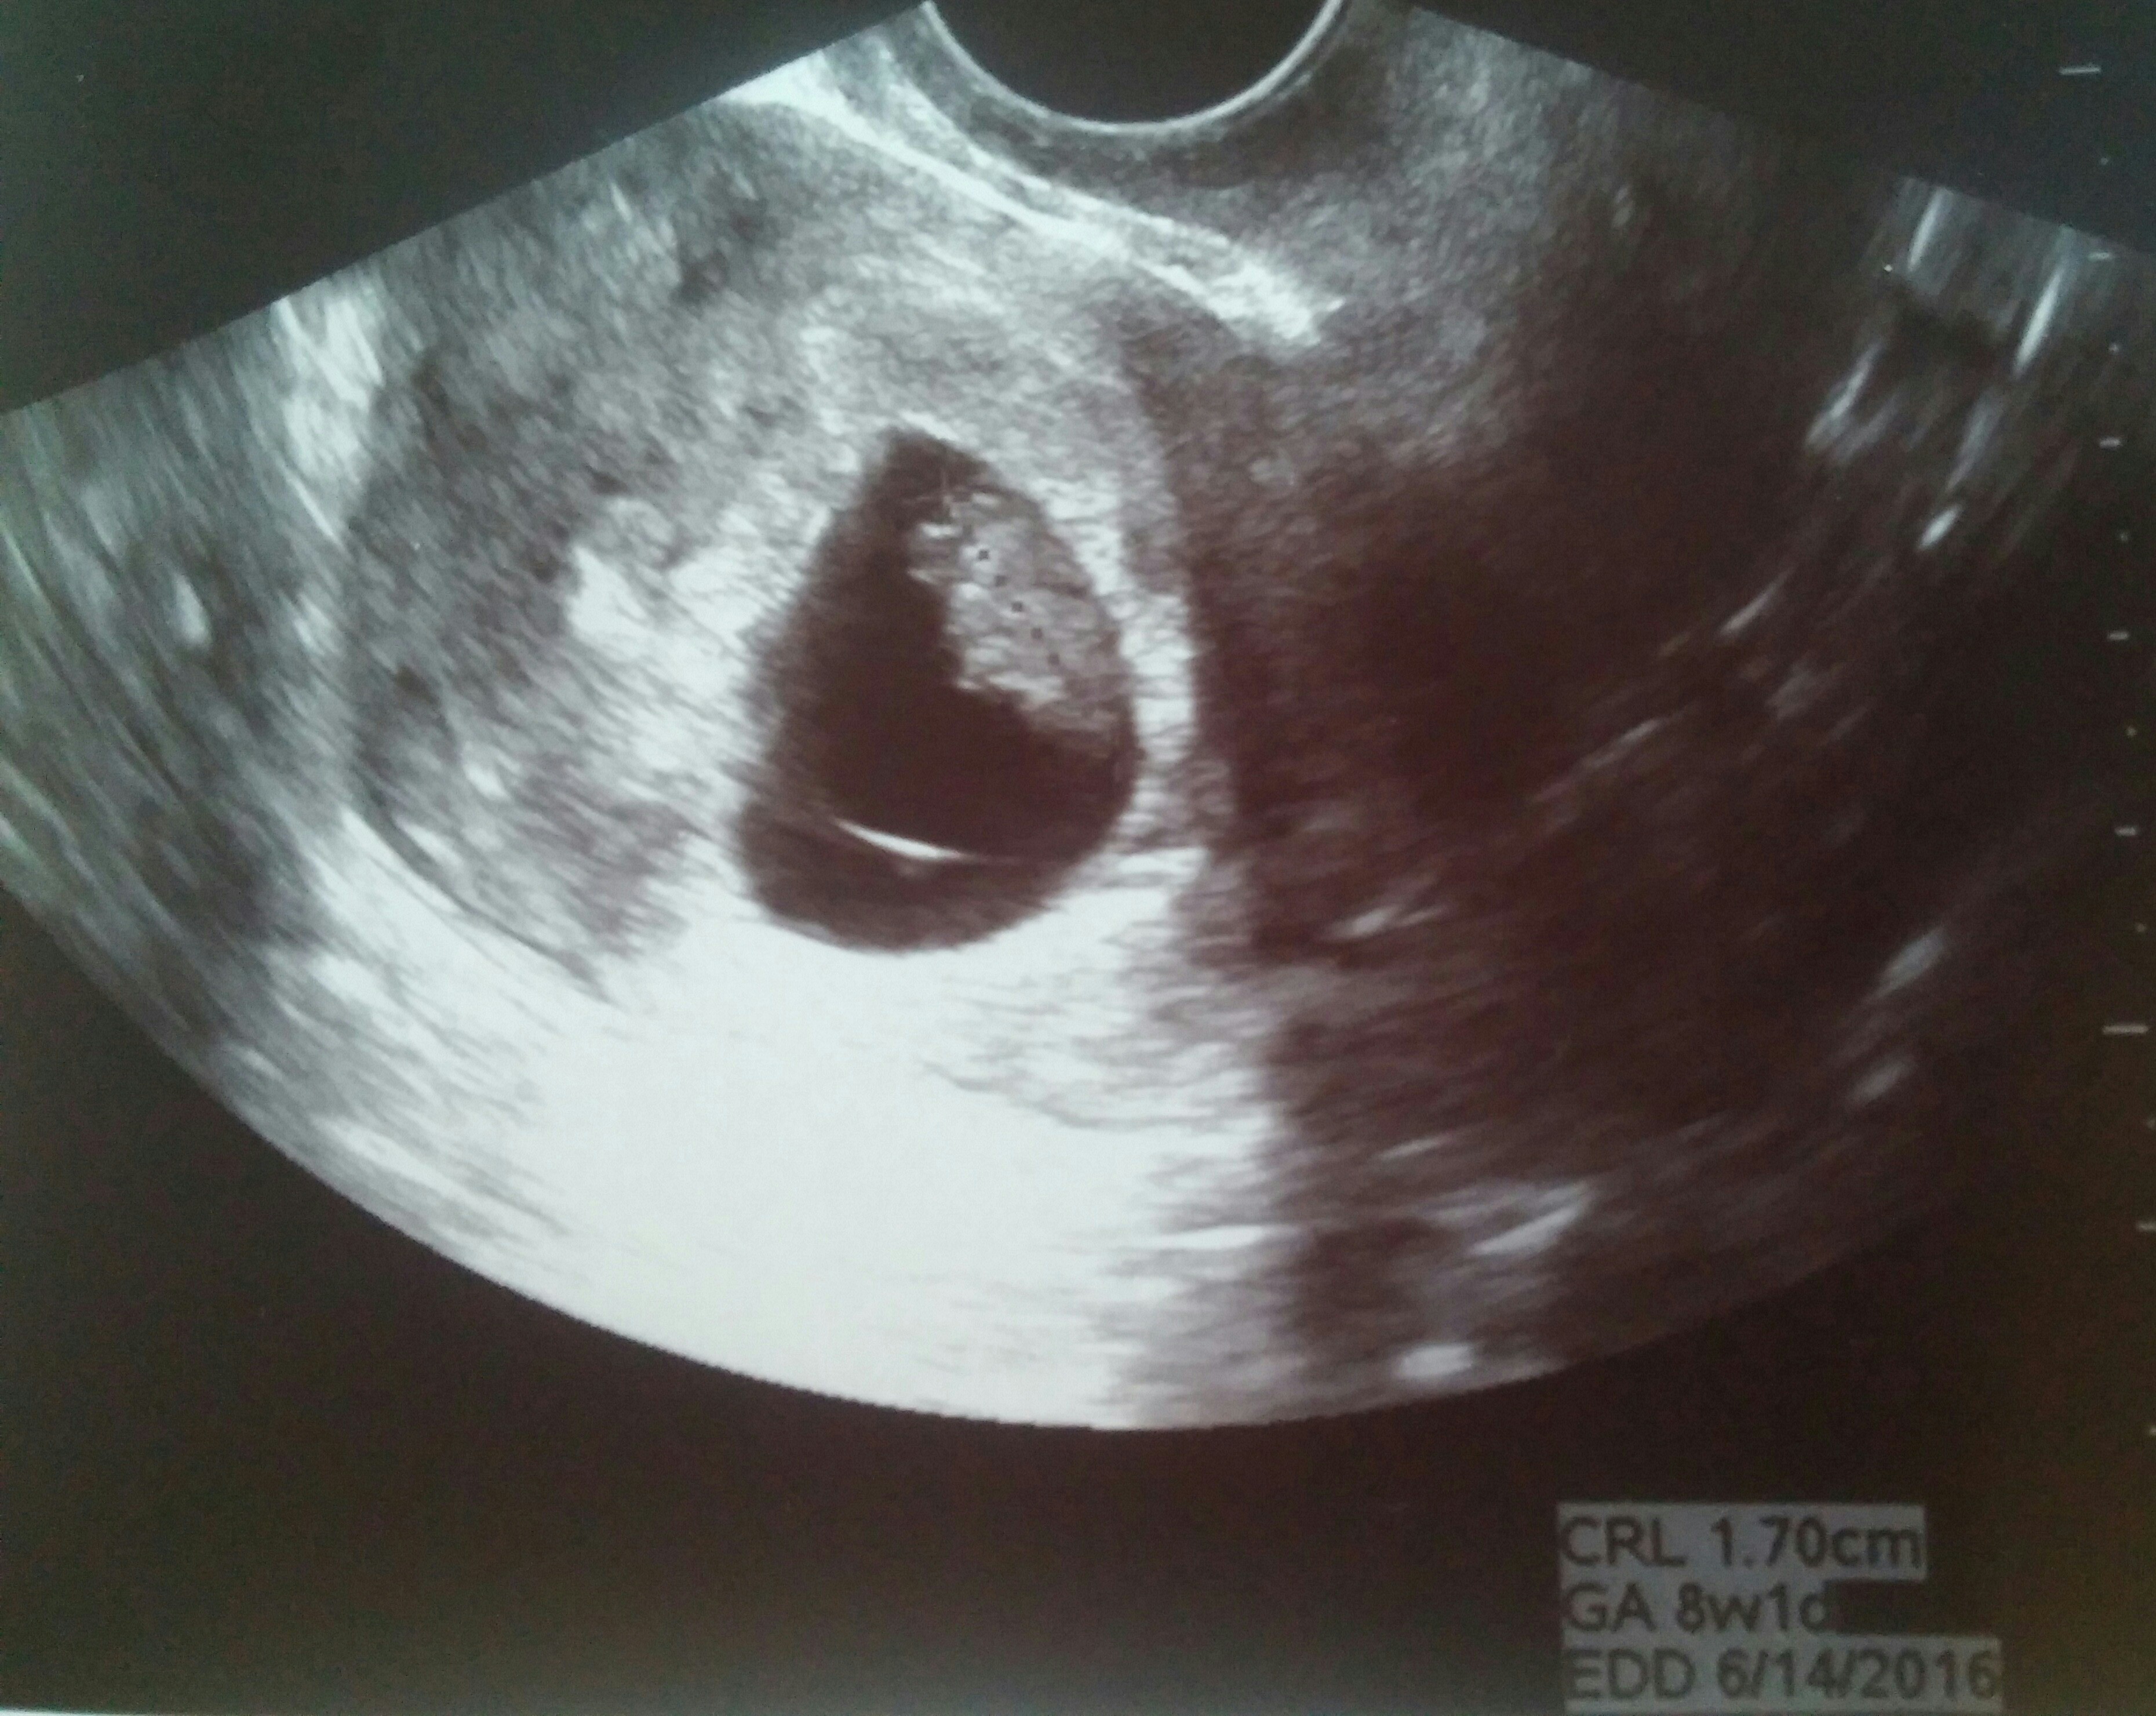

Had our first US today! Exactly 8w (LMP had me at 7w6d) and heart beat was a strong 163. All looks healthy & good. Next US is at 12w (NT scan). A bit relieved that all is well.